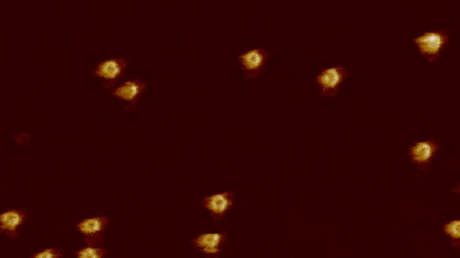

En una investigación de 2016, los investigadores británicos estudiaron el ataque del MAC a una membrana bacteriana y observaron que tras el contrataque de ese mecanismo de defensa la membrana presentaba numerosos poros. Estos orificios son increíblemente pequeños: su diámetro es de solo 10 nanómetros.

En el marco del nuevo estudio, crearon una superficie bacteriana modelo a partir de los lípidos de E. coli. Luego liberaron las proteínas MAC y filmaron todo el proceso mediante microscopía de fuerza atómica rápida, una forma de microscopía de muy alta resolución que permite obtener imágenes a nanoescala.